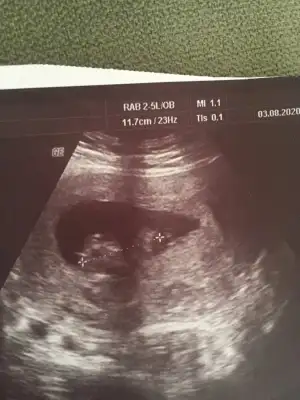

Merhaba kızlar 10+4 haftalık olduk bugün mecburen doktora gittim iki gündür kanlı ishal oldum hastane de serum taktılar kadın Doğua da gittim bebek iyi dedi doktor doktorum cinsiyetle ilgili hiç yorum yapmıyor nuba göre cinsiyet tahmini yapabilen arkadaşlar bi yardımcı olsanız

Resmî yükledim

• 94265E6D-7B26-4049-BC78-C3E5E71FFD37.webp

94265E6D-7B26-4049-BC78-C3E5E71FFD37.webp

42,3 KB · Görüntüleme: 35